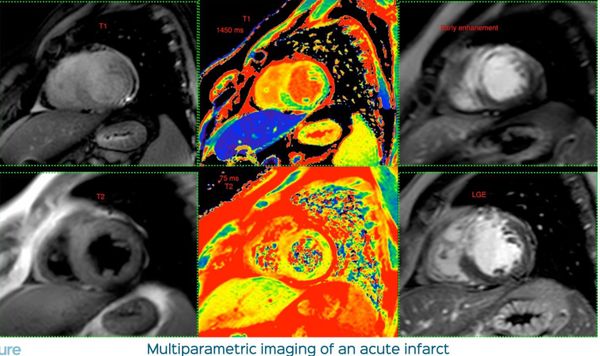

CMR brings so much more to the table in the setting of infarct and viability imaging as compared to FDG-PET

The additional uses of T1 mapping

The changing role of viability imaging including CMR

RCA infarct involving the LV and RV